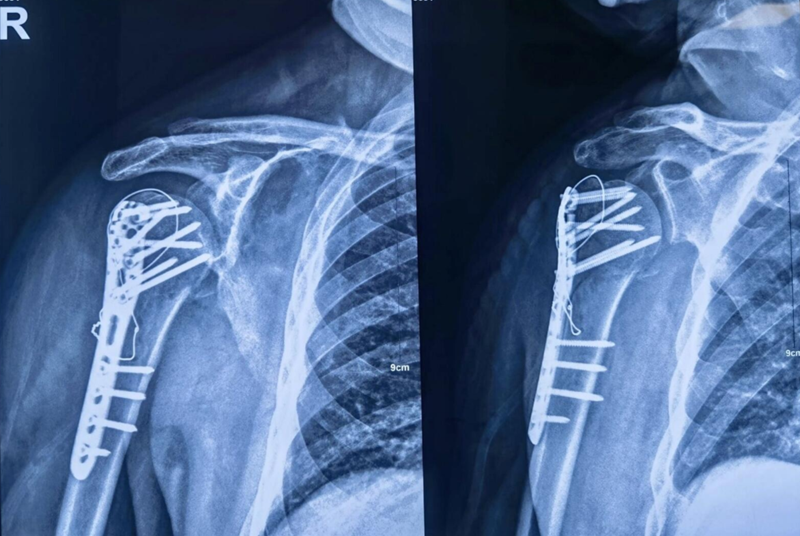

术中大幅度肩关节屈伸与外展内收活动,提示骨折坚强固定。

图19 术后X片